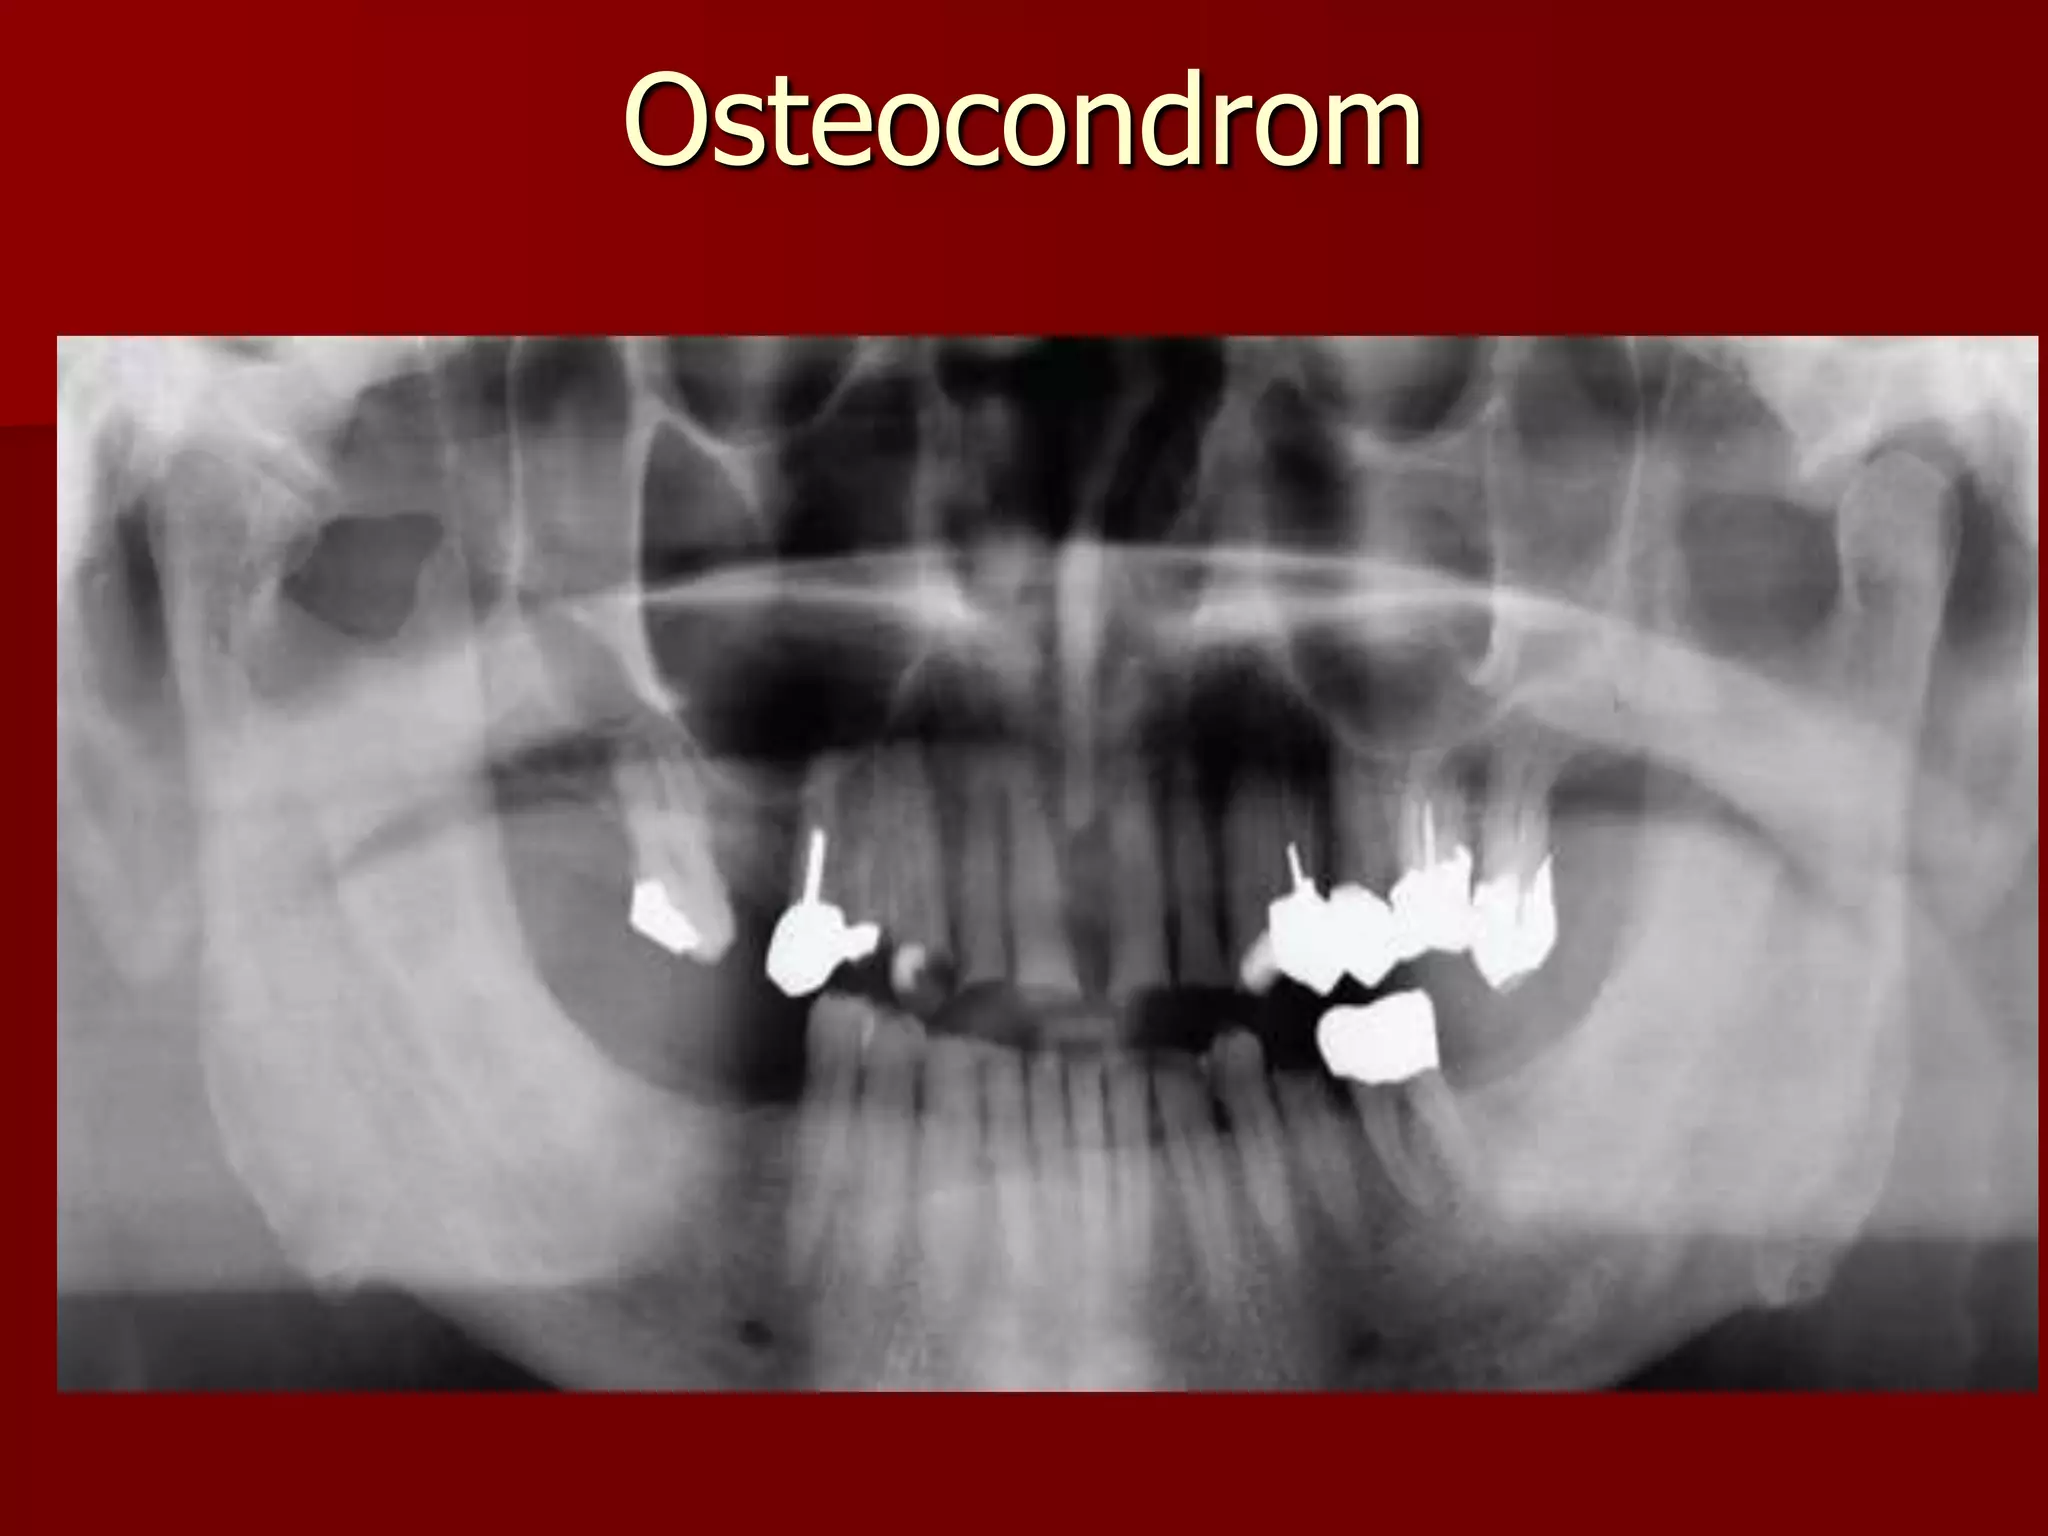

Tumorile ATM

Tumori benigne:

- cel mai frecvent - osteomul condilului

mandibular cu mărirea de volum a

acestuia şi deformare (depăşind

cavitatea glenoidă).

Diagnostic diferenţial:-hiperplazia de

condil (mărit dar nedeformat )

Alte tumori benigne :

- condromul

- osteocondromul

52

Incidenţă “faţă joasă” :

osteocondrom al condilului

mandibular stg.

Tomografie plană a A.T.M. stg. :

osteocondrom cu scleroză

reacţională în jur (inflamaţie) şi

leziuni artrozice

Osteocondrom